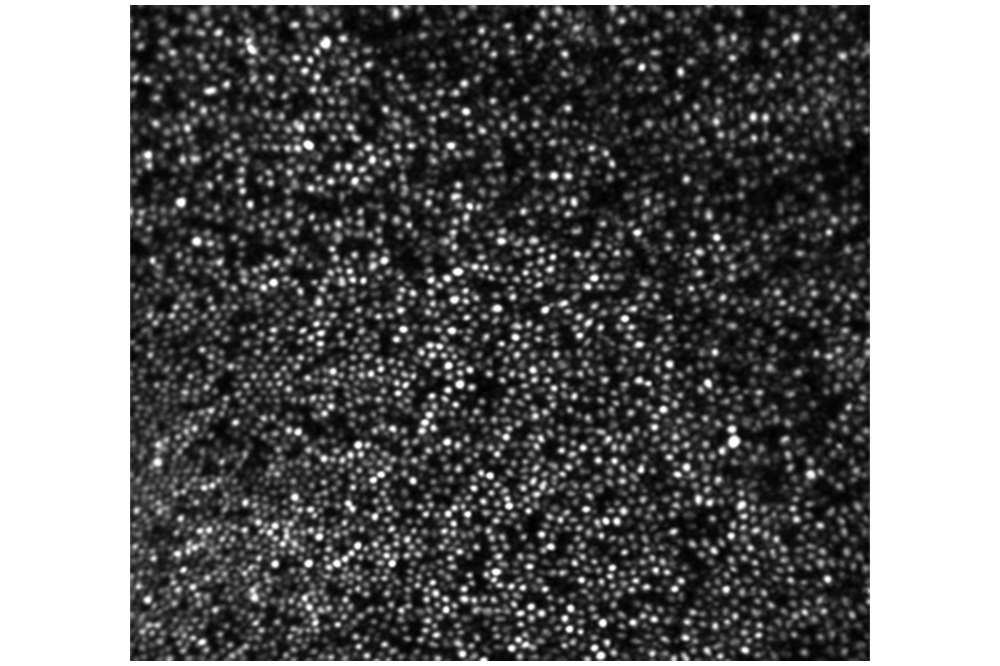

Peripheral Photoreceptor

Peripheral photoreceptor mosaic image generated by registering and averaging images taken over a span of 2 hours. The small cells are rods, larger cells are cones.